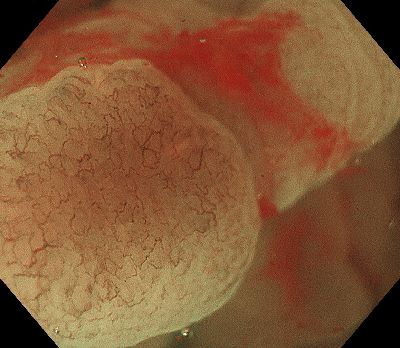

4mm大のポリープがあります。

近づいて顕微鏡機能で表面を観察しますが、表面の模様ははっきりしません。

ボタン1つでNBI画像が得られ表面の模様が簡単に観察できるようになりました。

これは”腺腫“と呼ばれる腫瘍です。ですが良性の腫瘍ですので大きいものを切除の対象としています。この方は他に切除するポリープがあったためこのポリープもついでに切除しました。

このNBI機能があるおかげでポリープの性質をすみやかに診断し切除の必要があるかどうか判断できます。